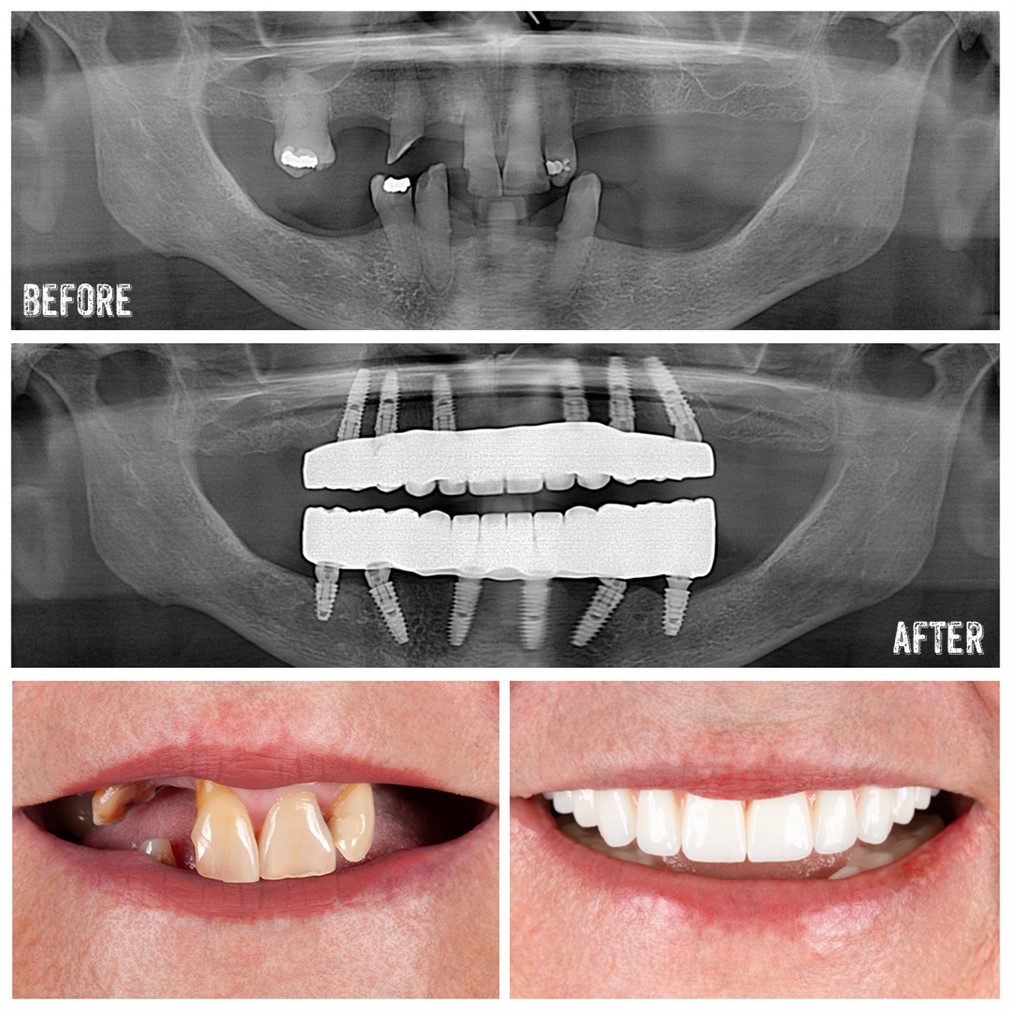

Yes, you can still get a dental implant 10 years after a tooth extraction, but if the bone has deteriorated, a bone graft may be required to create a stable foundation for the implant.